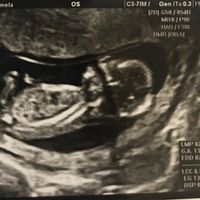

Buongiorno a tutte! Ho scoperto venerdì il mio positivo...oggi sono a 4+4 e la mia dpp è il 3 aprile 2020. Mi sa che sono la prima! Sono emozionatissima! Adesso aspetto con ansia il 20 agosto per fare...

Mi sa che sono la prima!!! la mia dpp è 5 marzo.... oggi sono a 4+5 .... ho qualche crampetto basso ventre ogni tanto.... poca fame ( cosa strana per me visto che di solito mangio anche i piedi del...